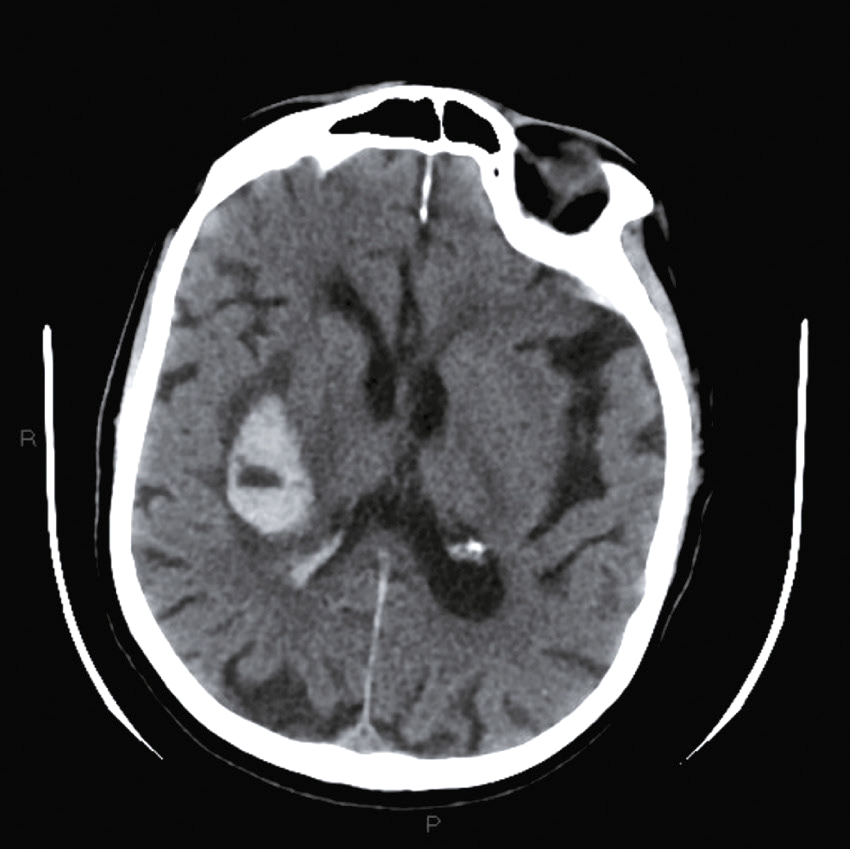

Question 4 – QRMVoici une coupe axiale d’un scanner cérébral sans injection (fig. 31.9). Concernant son interprétation, quelle(s) est (sont) la (les) proposition(s) exacte(s) ?

Fig. 31.9 L'image montre une coupe transversale d'un scanner cérébral (CT scan) d'un cerveau humain. Cette image en noir et blanc présente des détails anatomiques du cerveau, y compris les structures internes et les contours du crâne. Les zones claires représentent les tissus osseux, tandis que les zones sombres indiquent les tissus mous du cerveau. On peut observer des variations dans les nuances de gris qui révèlent différentes densités de tissus. Les ventricules cérébraux, qui sont des cavités remplies de liquide céphalo-rachidien, sont également visibles au centre de l'image. Ces cavités apparaissent sombres en contraste avec les tissus environnants. La partie périphérique de l'image montre les os du crâne, apparaissant comme des lignes blanches bien définies. Les scanners cérébraux sont des outils essentiels pour diagnostiquer et surveiller diverses conditions neurologiques. Ils permettent de détecter des anomalies telles que des hémorragies, des tumeurs ou des lésions cérébrales. Les variations de teintes visibles sur l'image aident à différencier les structures et à évaluer leur état, fournissant ainsi des informations cruciales pour les professionnels de la santé. Grâce à ces images détaillées, il est possible de planifier des traitements adaptés et de surveiller l'évolution des pathologies cérébrales.

- A hyperdensité spontanée des vallées sylviennes

- B hyperdensité spontanée du sinus maxillaire droit

- C hypodensité spontanée de l’épiphyse

- D hyperdensité spontanée du 4e ventricule

-

E hypodensité spontanée des plexus choroïdes